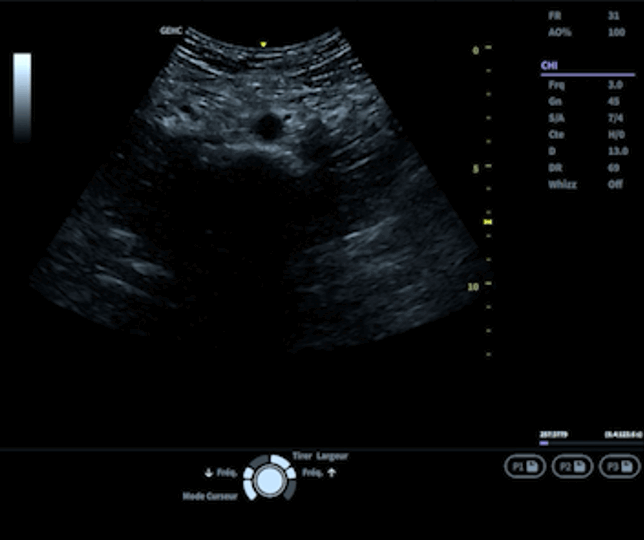

2. Réalisation des coupes échographiques

• Coupe transversale : Descendre en coupe transversale depuis l’aorte au niveau des artères rénales jusqu'à la bifurcation iliaque. Si aucune modification du diamètre n’est observée, remonter 1 cm au-dessus de la bifurcation. La sonde est alors généralement positionnée juste au-dessus de l’ombilic. Sur l’image de l’aorte ainsi obtenue, mesurer le diamètre antéro-postérieur transverse. Une mesure inférieure à 30 mm exclut le diagnostic d’AAA. Si une modification du diamètre est observée, mesurer le diamètre antéro-postérieur transverse le plus grand. Cette mesure doit être effectuée sur 3 acquisitions différentes.

• Coupe longitudinale : Cette vue confirme la mesure transversale en offrant une évaluation complémentaire.

Les médecins doivent également être vigilants aux artéfacts échographiques (voir glossaire) susceptibles de compliquer l’interprétation, comme le cône d’ombre postérieur ou le renforcement postérieur.